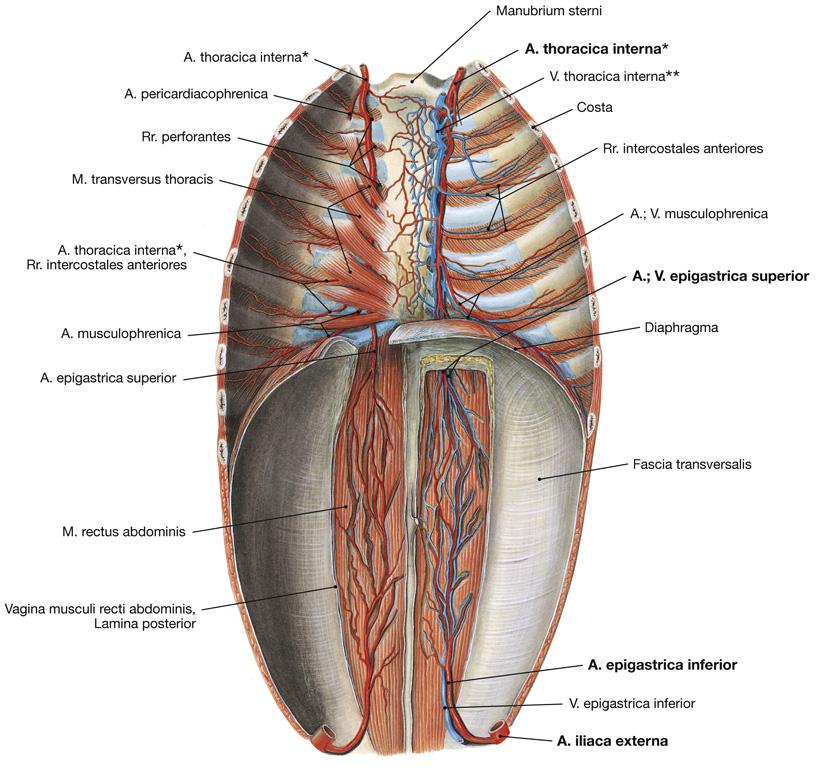

Fig 3.16: a. thoracica interna

|

|

Fig 3.19: Diaphragma

pars sternalis pars costalis pars lumbalis centrum tendineum hiatus aorticus hiatus oesophageus v cava inferior a thoracica interna

|

|